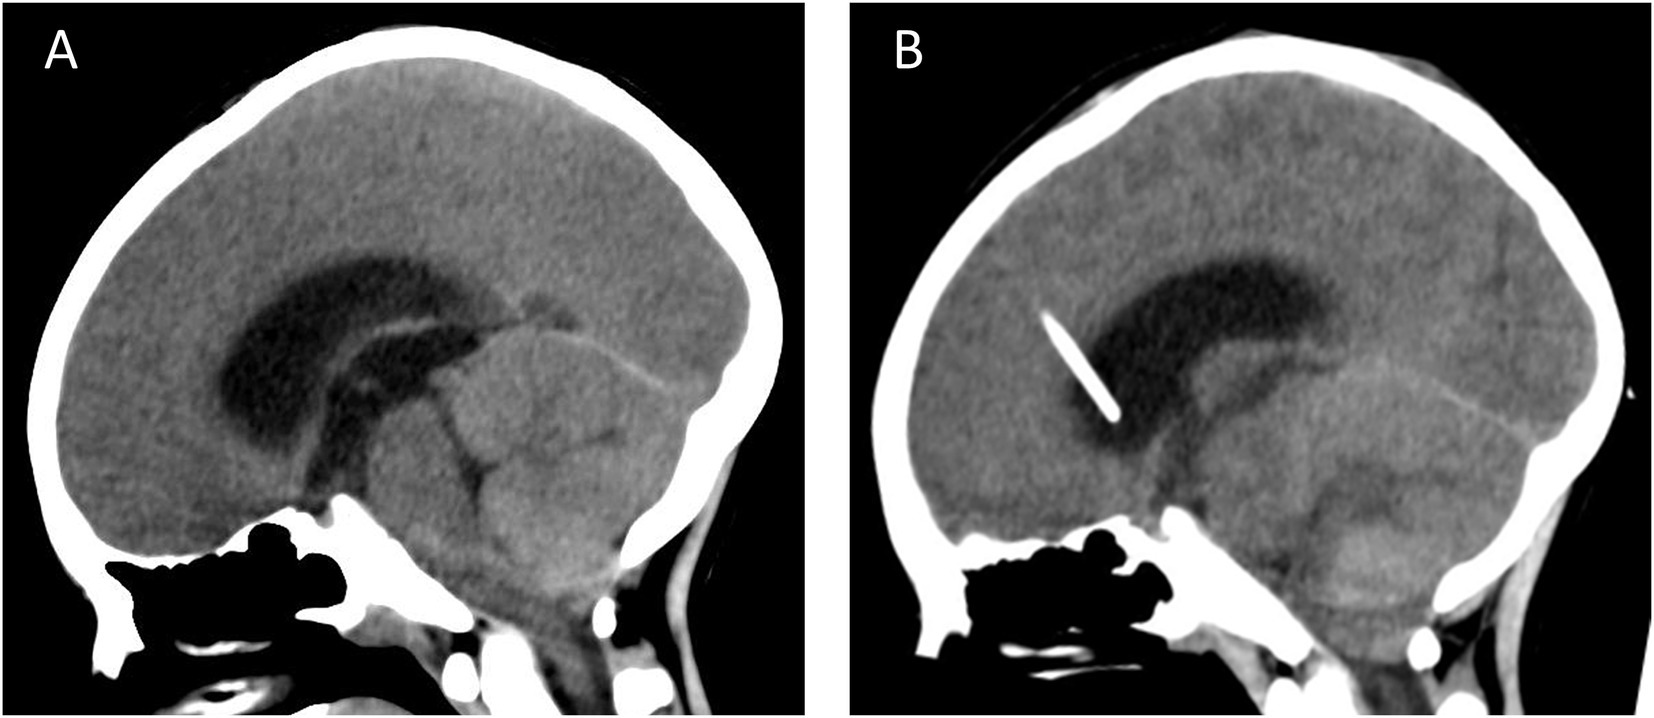

The patient, a male, 8 years old, entered another hospital with intermittent headache with nausea and vomiting, and a cranial MRI showed cerebellar swelling in the posterior cranial fossa, which was initially diagnosed as meningitis. However, after symptomatic treatment, the symptoms did not improve significantly, so he was referred to our hospital for further evaluation and treatment. Upon admission to our hospital, physical examination showed that the patient had no fever, poor mental status, and no clear neurologic abnormality. Computed tomography angiography (CTA) findings suggested a subcerebellar tonsillar hernia (Figure 1A) with severe hydrocephalus. Based on the imaging findings and combined with the MRI images provided by the patient’s family, it was decided to perform emergency Ommaya bursa placement and drainage on the same day after comprehensive evaluation to relieve intracranial pressure. Postoperative follow-up cranial CT showed no significant improvement in hydrocephalus, and no other abnormalities were detected (Figure 1B).

Figure 1. CT examination (A) the cerebellar tonsils moved downward beyond the greater occipital foramen to the atlantoaxial level, and the diagnosis of subcerebellar tonsillar hernia combined with supratentorial obstructive hydrocephalus was made; (B) on examination after the emergency Ommaya capsule placement and drainage surgery, the subcerebellar tonsillar hernia and supratentorial hydrocephalus had not yet been relieved, and the placement of a drainage tube was seen in the lateral ventricle.